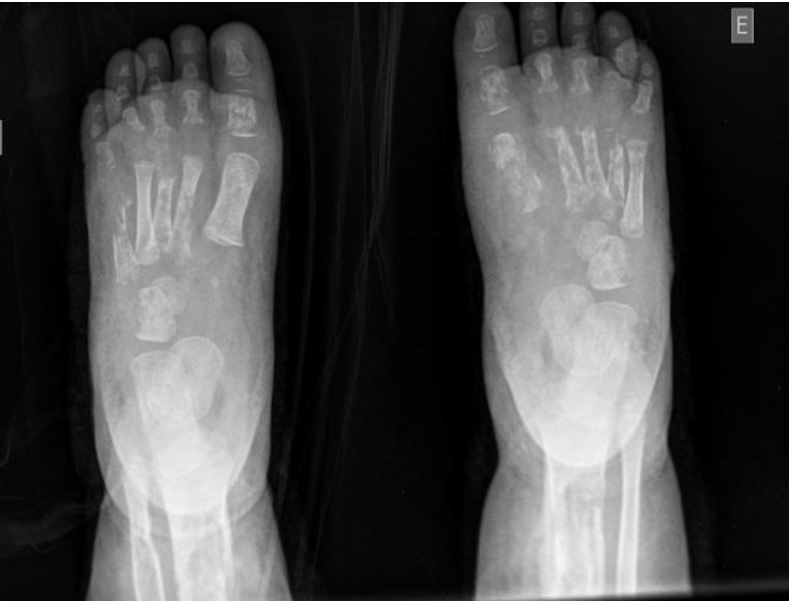

Em ultrassonografia de membros inferiores, foram confirmados abscessos nos pés. Na investigação, foi diagnosticada a osteomielite que acometia úmero, tíbia, ossos dos pés e das mãos bilateralmente. Foi feita drenagem contínua de lojas de secreção purulenta na região das tíbias.

As radiografias confirmaram o diagnóstico de osteomielite (Figuras 1 a 5). Em culturas de secreção tibial, foram isolados Escherichia coliESBL e Proteus mirabilis, sensíveis a imipenem e amicacina. Dessa forma, optou-se por tratamento com antibioticoterapia parenteral, ao longo de tempo prolongado de internação.

Foram realizadas radiografias seriadas e o consequente tratamento cirúrgico de drenagem de abscessos e colocação de drenos. Não foram realizadas cintilografias e ressonância magnética, uma vez que o diagnóstico se fez tardiamente com o quadro já instalado de forma importante. Esses últimos exames contribuiriam para um diagnóstico mais precoce. Não foi realizada biópsia óssea das áreas acometidas, exame eventualmente necessário1. Em alguns casos, radiografias podem estar normais4, porém, em outros, como no caso descrito, elas se apresentam alteradas, conforme visto nas imagens.

Em seguimento ambulatorial, o paciente apresenta padrão radiológico melhor, como evidenciado em radiografia recente, ausente o atraso no crescimento, uma vez que placas epifisárias não se mostram afetadas. Permaneceu em antibioticoterapia estendida por mais cinco meses além do programado na alta hospitalar e isento de complicações novas por osteomielite. Internações devido às crises álgicas ou outros tipos de infecções já foram registradas.